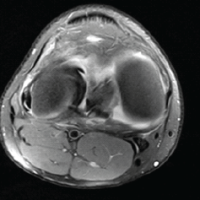

Computed tomography scan and magnetic resonance imaging of the left hip were done to assess the viability of the head. The femoral head was rotated and slightly deformed with complete loss of articular cartilage without any evidence of avascular necrosis of the head of the femur. The posterior wall of the acetabulum appeared fragmented, and the anterior wall was also deformed (Fig. 3).

Figure 3: (a) Computed tomograph Images showing posterior superior dislocation of the left femoral head with the posterior column of left acetabulum appears fragmented; (b) Magnetic resonance imaging images showing complete loss of articular cartilage without any evidence of avascular changes in the femoral head.